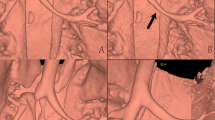

Measurements of the objective image quality in the head and neck of two 12-year-old boys reconstructed with the FBP algorithm and the IMR algorithm. The ROIs for the CT values and noises were measured for both FBP/IMR groups in the origin of the bilateral CCA (A/a) and ICA (B/b) and the bilateral M1 segments of the MCA (C/c). The CPR is shown in column (D/d). The CT values of the ROIs of the IMR group were significantly higher (566.8, 546.2 and 531.1 HU) than those of the FBP group (319.8, 356.9 and 295.1 HU) (p < 0.001), whereas the image noises were significantly lower in the IMR groups than those in the group FBP (p < 0.001). Abbreviations: FBP, filtered back projection; IMR, iterative model construction; ROI, region of interest; CCA, common carotid artery; ICA, internal carotid artery; MCA, middle cerebral artery; CPR, curved planar reconstruction. R, right; L, left.

Measurements of the subjective image quality in the head and neck CTA of two 12-year-old boys reconstructed with the FBP algorithm and the IMR algorithm. (A,B) show the VR and MIP images of the FBP group, while a and b show the VR and MIP images of the IMR group. The subjective image qualities of both groups were rated as excellent (p < 0.01). The IMR group obtained a better image quality than that of group A (p < 0.01). Abbreviations: VR, volume rendering; MIP, maximum intensity projection.

Following the random and double-blind method, two senior radiologists (visiting staff) reviewed and evaluated the images (including the objective and subject evaluation) of all the patients independently. Three circular ROIs were selected bilaterally for each patient, which were the origin of the CCA (7 mm2), the origin of ICA (7 mm2) and the M1 segment of the MCA (3 mm2) (Fig. 2). Then, we (1) measured the enhanced CT value (CTv) of the ROIs, avoiding touching the vascular wall and calcified plaque. The image noise was defined as the standard deviation value (SDv) of the ROIs. (2) We measured the mean CT values (CTm) of the bilateral paravertebral muscles or the temporal muscle of the abovementioned ROI levels. (3) The SNR and CNR were calculated by the following formulas: SNR = CTv/SDv and CNR = (CTv − CTm)/SDv.